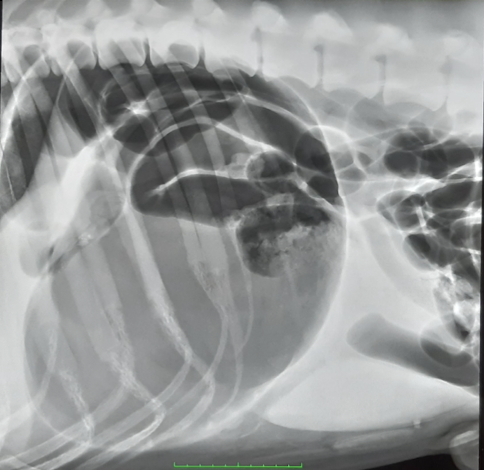

how do you diagnose GDV?

A

Radiography - unstable patient so single view

Right lateral abdo